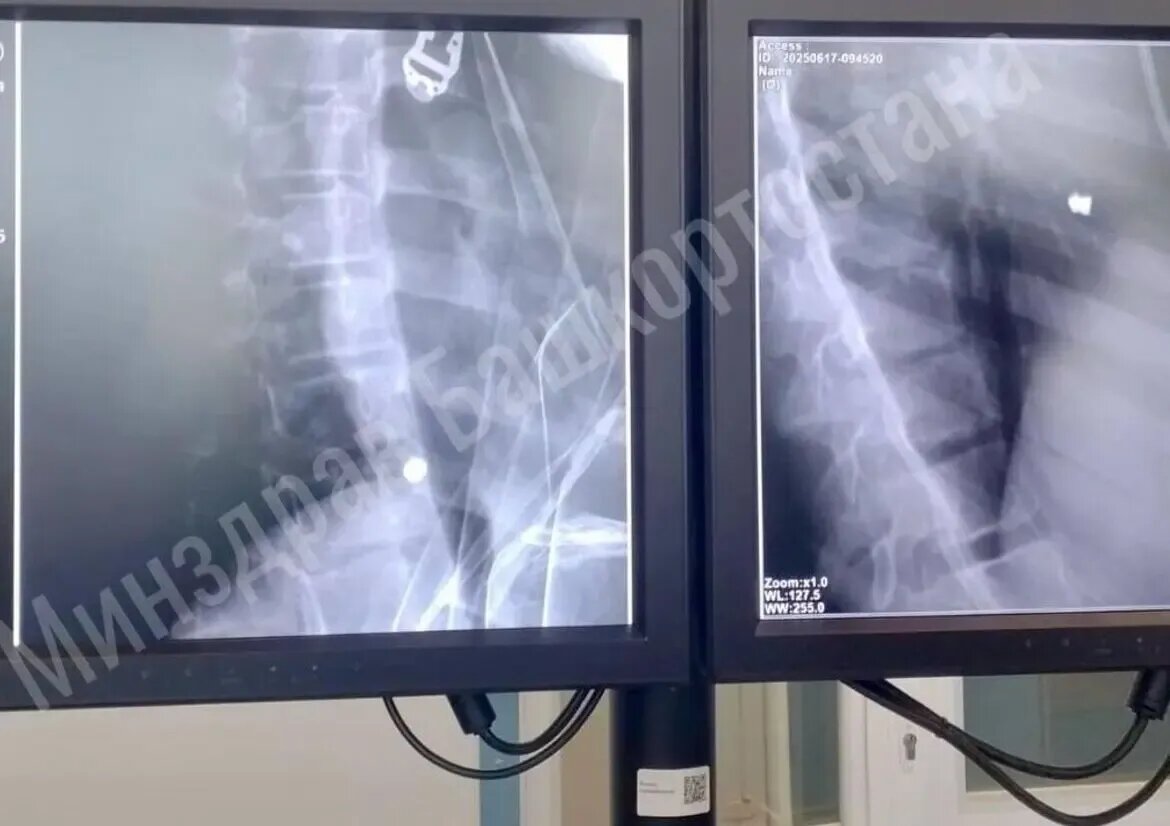

Невероятное спасение: ребенок выжил после пулевого ранения сердца

Башкирским медикам удалось спасти 11-летнего ребенка с пулевым ранением сердца. Серьезную травму девочка получила по неосторожности, следует из заявления главы Минздрава РБ Айрата Рахматуллина.

Чрезвычайное происшествие случилось на территории Иглинского района. Министр сообщил, что это был несчастный случай.